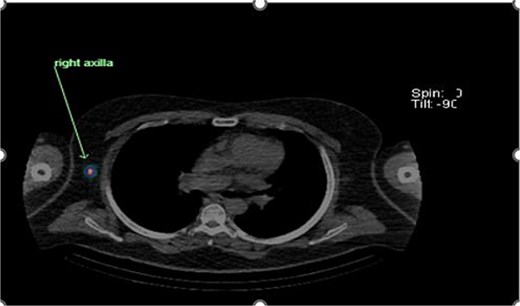

Preoperative lymphoscintigraphy was performed to detect the sentinel lymph node (Fig. 1), expecting it to be in the right inguinal region (Fig. 2). However, drainage to both the right axillary (Fig. 3) and inguinal areas was demonstrated. During surgery, a gamma camera confirmed drainage to both regions (Fig. 4). Blue dye was injected around the previous scar, and sentinel nodes were dissected guided by both blue dye and gamma camera for histopathology.

Lymphoscintigraphy showing drainage from the right lower back lesion.